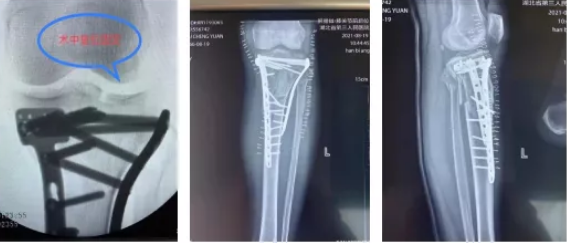

到达医院后,关节创伤骨科值班医生袁文泽和主治医师刘超迅速接诊,在查看伤情后随即安排检查,X光结果提示:左膝胫骨平台内外后三个方向塌陷骨折,需要手术治疗。经过一个星期的跟骨牵引、消肿、止痛抗凝等治疗,吴师傅伤情稳定,10月18日,关节创伤骨科主任王显勋根据伤者具体情况,选择为其进行内外后三个方向钢板固定术,通过胫骨平台内外侧两块钢板巧妙恢复胫骨平台关节面的平整,同时将骨折固定牢靠,两个小时后吴师傅被顺利推出手术室。

(术中、术后X光片)